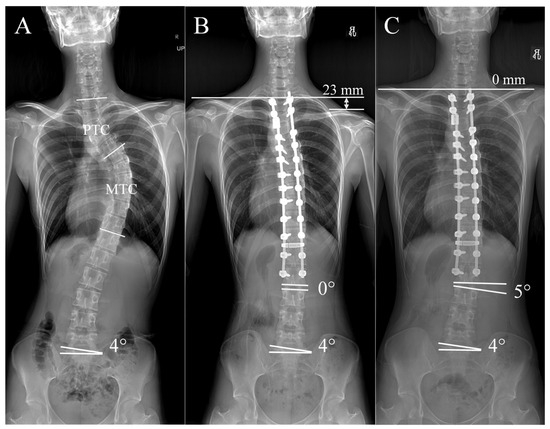

| PTC | Proximal Thoracic Curve |

| MTC | Main Thoracic Curve |